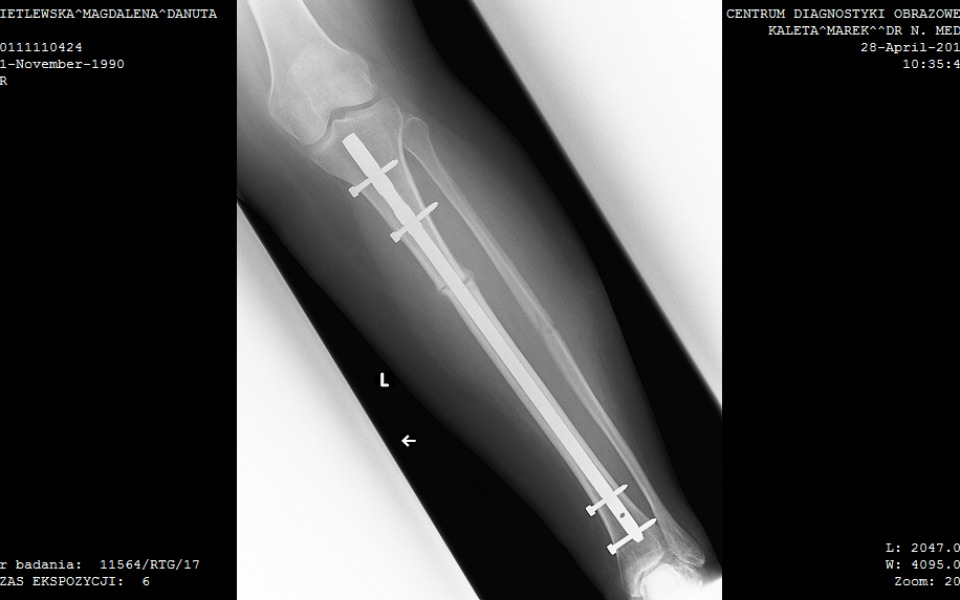

Witam, nazywam się Magdalena i mam 32 lata. Moje problemy zdrowotne zaczęły się już w wieku 4 lat gdzie w wyniku pękniętego wyrostka dostałam sepsy. Nie dawano mi szans na przeżycie ale się udało. Później doszły alergie i również astma oskrzelowa. Najgorsze zaczęło się w wieku 12 lat zaczęłam coraz bardziej utykać i zdiagnozowano u mnie złuszczenie głowy kości udowej lewej,noga była krótsza o kilka cm. Leczenie które u mnie zastosowano to zespolenie kości udowej za pomocą śruby kaniulowanej. Moje biodro zostało unieruchomione co utrudniało mi codzienne życie. Siedzenie czy nawet zawiązanie buta było dla mnie ogromnym wyzwaniem. Noga po mimo leczenia coraz bardziej skręcała się do wewnętrznej strony. W wieku 18 lat przeszłam operację usunięcia woreczka żółciowego który wysiadł mi w wyniku zażywania leków przeciwbólowych. Również w wieku 18 lat śruba z biodra została usunięta. Później dowiedziałam się że muszę przejść operację wstawienia endoprotezy biodrowej. W kolejce czekałam aż 5 lat gdzie stan mojej nogi uległ pogorszeniu, moja kość biodrowa była praktycznie starta do zera. Po operacji endoprotezy biodra ciężko do siebie dochodziłam. Po wybudzeniu nie miałam czucia w nodze co utrzymywało się prawie przez pół roku.Po operacji moja noga na odcinku udowym została wyprostowana ale od kolana w dół była dalej skręcona do środka. Lekarz zalecił kolejną operację jaką było wyprostowanie nogi poniżej kolana. Na operację czekałam kolejne 2 lata. Niestety operację przeszłam fatalnie, noga zaczęła bardzo puchnąc, pani która ściągała szwy zignorowała to, co skutkowało tym, że miałam głębokie otwarte rany. Codziennie musiałam przyjeżdżać do szpitala na założenie plastrów które zespajały otwartą ranę. Noga była tak spuchnięta że moja stopa dosłownie była czarna. Lekarz zalecił na "Cito" wizytę u chirurga naczyniowego ale lekarz bo badaniu usg nic nie stwierdził. Rany po mimo braku infekcji ciężko się goiły. Lekarz stwierdził że pewnie mój organizm próbuje odrzucić ciało obce z organizmu więc stąd te dolegliwości.W kolejnych latach usunięto mi wszystkie gwoździe z kości piszczelowej. Niestety problem z brakiem czucia w nodze a jednoczesnym bólem nie został rozwiązany. Noga dalej była mocno spuchnięta więc lekarz zalecił kolejną wizytę u chirurga naczyniowego ale i tu nie stwierdzono przyczyny a jedynie przypuszczenie że być może naczynia limfatyczne zostały uszkodzone. I tak zostałam bez żadnej diagnozy i leczenia. Próby leczenia w innych placówkach się nie udały bo każdy lekarz mówił że mam sobie iść do lekarza który mnie operował bo oni po kimś robić nie będą. Mój stan teraz jest kiepski, nie tylko noga jest bardzo spuchnięta, jest dwa razy większa od prawej nogi, ale puchnie mi cała lewa strona ciała. Mój kręgosłup który się skrzywił przez to ,że przez tyle lat chodziłam o krótszej nodze również mocno daje o sobie znać, ból często jest nie do zniesienia, czasami nawet promieniuje do klatki piersiowej co jest najbardziej bolesne. Za kilka lat znowu muszę przejść operację wymiany endoprotezy która starcza na około 10 lat. Nie posiadam prawa do renty dlatego, że dyrekcja szkoły powiedziała w prost ,że jeżeli będę uznana za osobę niepełnosprawną to nie mam prawa uczyć się placówce która nie jest dostosowana, nawet nie miałam prawa wejść na teren szkoły o kulach a w tamtych czasach nie było takiej szkoły w pobliżu mojego miasta więc renta przepadła. Od MOPSu też nie dostałam żadnej pomocy. Boję się o swoją przyszłość. Wiem, że jestem dużym obciążeniem dla moich rodziców,moja psychika jest na wykończeniu dlatego zwracam się z prośbą o wsparcie do państwa. Zebrane pieniądze przeznaczyłabym na leczenie,usamodzielnienie się i na życie.